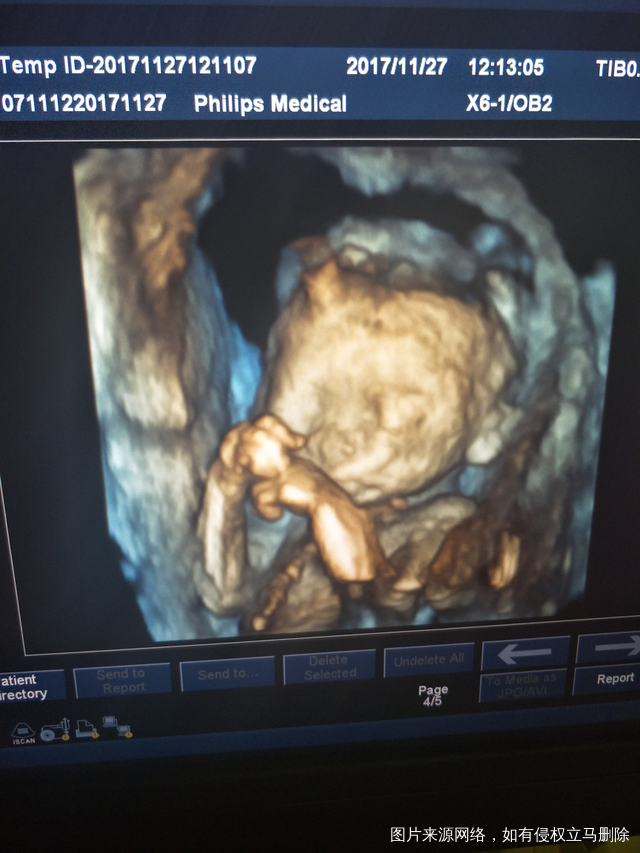

麻烦医生看看宝宝怎么样,会不会严重偏小。